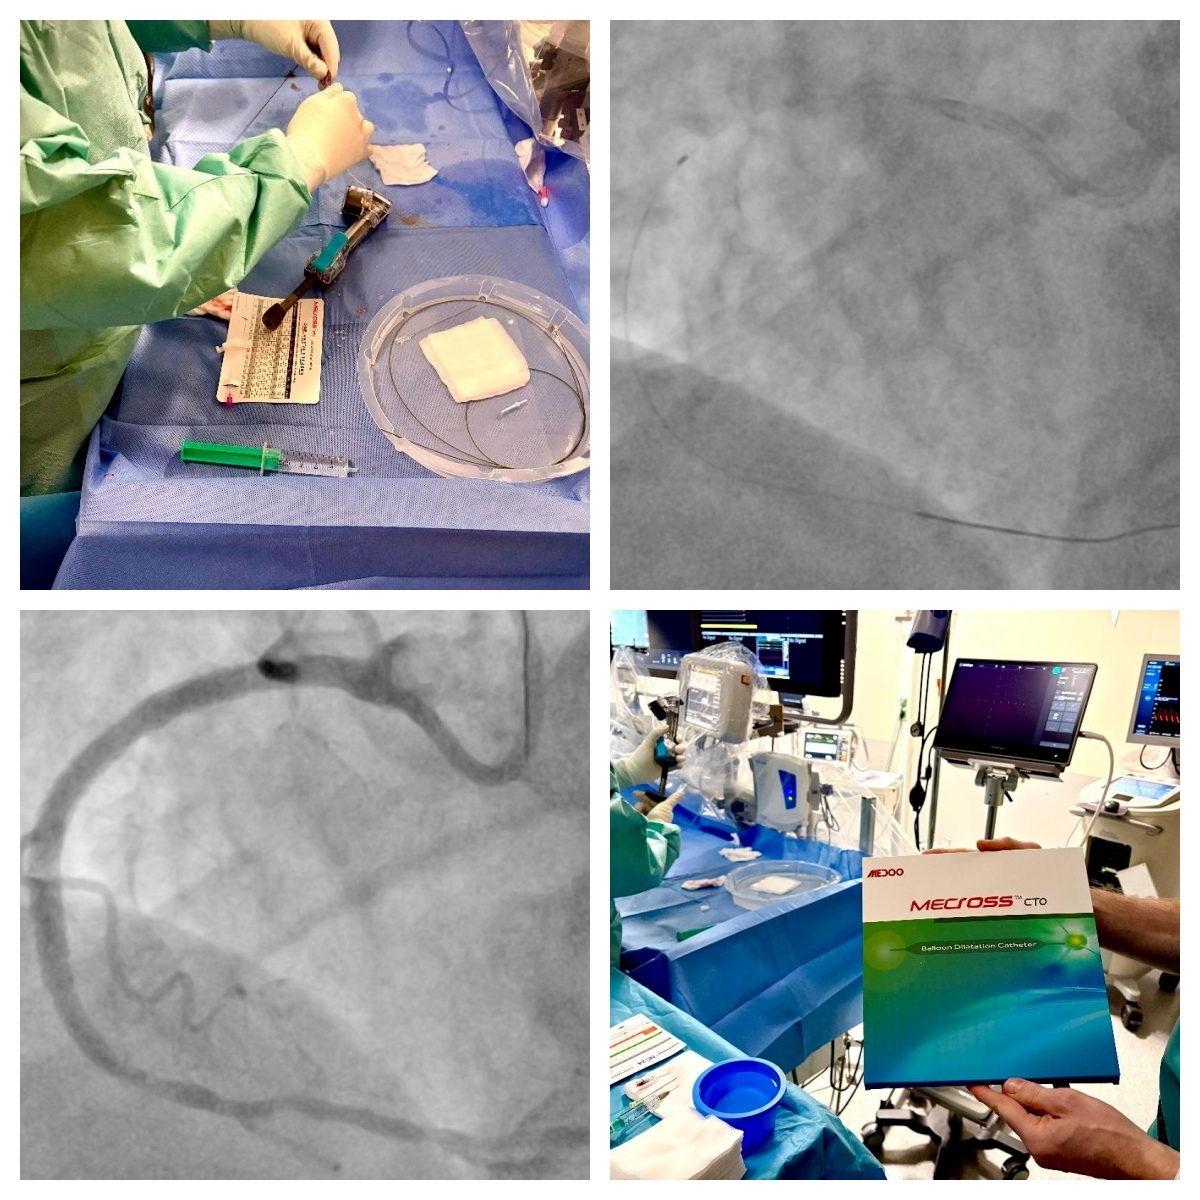

72 岁男性劳力型心绞痛患者,右冠状动脉中段慢性完全闭塞(J-CTO 评分 2 分),病变近端帽部钝性、体部钙化,属于中等难度介入病变,采用顺行导丝升级策略进行手术。

导丝顺利通过闭塞段后,选用Medoo MeCross CTO半顺应性PTCA球囊扩张导管1.0mm 球囊进行初始病变预处理,球囊无阻力通过闭塞段并精准定位,充气后扩张充分,为后续器械操作奠定良好基础。整个手术过程中,Medoo球囊拆封简便、充放气顺畅稳定无延迟,无任何操作障碍,产品整体性能与国际一线品牌持平,助力手术顺利完成,最终造影显示病变部位血流通畅,效果优异。

80 岁女性劳力型心绞痛患者,排除急性冠脉综合征后,造影确诊左前降支 - 对角支分叉处临界狭窄,且病变部位重度钙化,血管内超声证实狭窄具有血流动力学相关性,需介入干预。

手术选用Medoo MeCross NC 非顺应性PTCA球囊扩张导管3.0×15mm对钙化病变进行预扩张,球囊轻松通过重度钙化狭窄部位,定位精准无偏差,充放气过程顺畅可控,推送性与跟踪性表现优异。